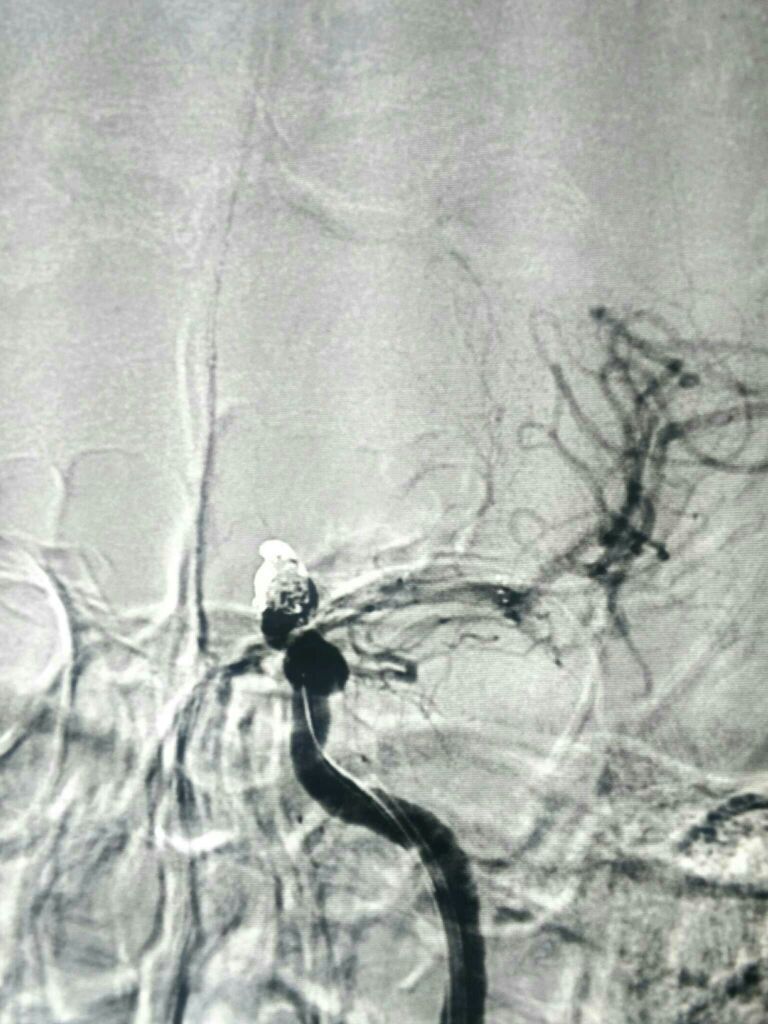

DSA左侧ICA“血泡”样动脉瘤

动脉瘤大小5.5*8mm

栓塞工作角度33/-28影像满意